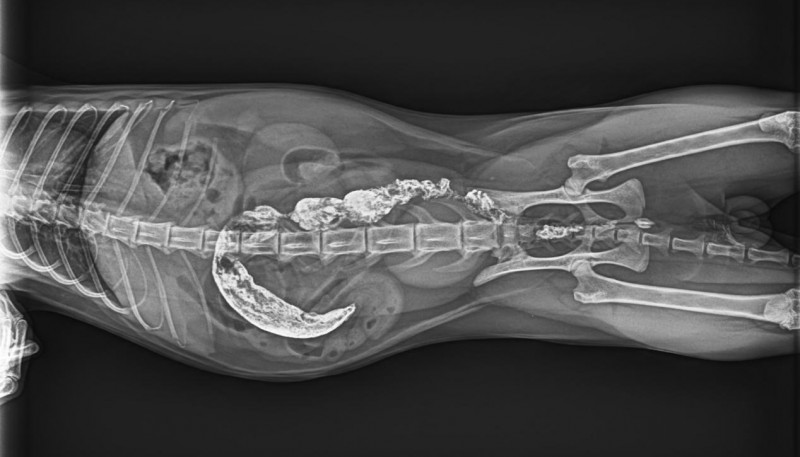

宠物诊疗中,最具挑战性的莫过于细微病灶的诊断——0.1mm的骨骼裂纹、豌豆大小的脏器结节、兔子歪斜过长的臼齿齿根,这些隐匿病灶往往是疾病的关键,却极易被常规DR的模糊图像忽略,导致漏诊、误诊。

必康宠物DR以实测数据彰显高清硬实力:经线对卡实测,成像分辨率均值可达3.7lp/mm,峰值可达4.0lp/mm,远超行业常规标准,细微到0.1mm的骨骼裂纹、脏器微小结节,甚至是纤细如发丝的血管、豌豆大小的淋巴结,都能清晰可辨。临床应用中,无论是小型犬的隐匿性骨折、猫咪的早期骨裂,还是兔子上臼齿牙根异常生长压迫眼球的复杂病例,必康DR都能精准捕捉病灶细节,清晰呈现病变位置、大小与形态,帮助兽医快速锁定病因,为后续治疗筑牢诊断根基。

某宠物医院接诊一只精神萎靡、眼球突出的兔子,疑似严重牙科疾病,常规DR拍摄的影像模糊,无法清晰呈现齿根状态,难以确诊。借助必康宠物DR的高清成像与AI器官分割功能,设备快速捕捉影像,清晰呈现兔子右臼齿的过长、歪斜,以及齿根穿透牙槽骨、压迫眼球后方的细节,AI伪彩增强进一步凸显病变区域,兽医几分钟内便精准确诊,为后续手术治疗争取了宝贵时间,也让宠主看到了希望。